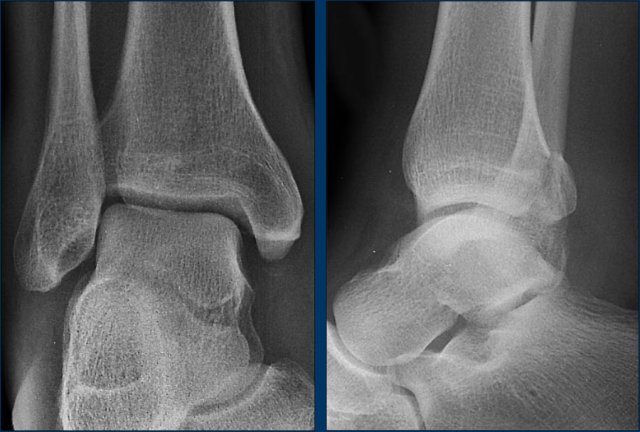

case 4 - ankle distortion

What are the findings?

What is the stage of this injury?